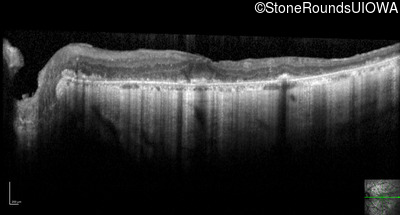

Optical Coherence Tomography - Left - 20/80 -1

Exemplar / OCT Stack